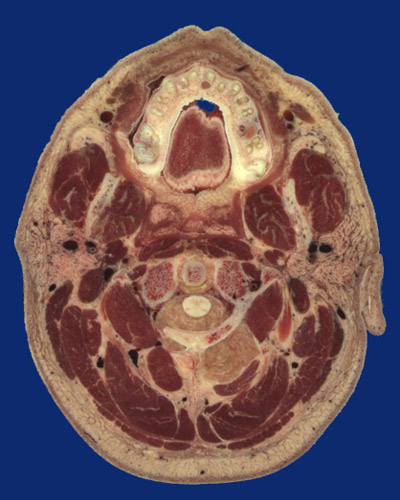

Identify the following regions in the image above: Orbicularis oris - Philtrum - Maxilla - Tongue - Premolar tooth roots (2) - Molar tooth roots (3) - Facial a. & v. - Mandibular ramus - Masseter - Parotid gland - Buccinator - Posterior belly of digastricus - Medial pterygoid - Styloid process - Styloid muscles (stylohyoid, stylopharyngeus, styloglossus) - Vertebral artery - Sternocleidomastoid - Splenius capitis - Trapezius - Semispinalis capitis - Rectus capitis posterior major - Obliquus capitis inferior - Rectus capitis lateralis - Rectus capitis anterior - Longus capitis - Superficial temporal artery of external carotid - Retromandibular vein - Internal jugular vein - Internal carotid artery - Articular process of C1 - Transverse ligament of atlas - Odontoid process of C2 (dens) - Cervical spinal cord